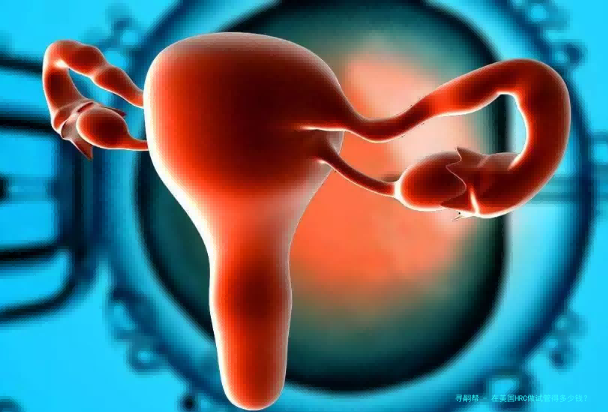

随着国内试管助孕患者的快速增长,越来越多的家庭须要试管婴儿。很多人都会关怀试管婴儿费用的问题,一般来说试管的费用会根据患者的详细情况而有所差异。哪样在美国HRC做试管得几何钱?费用明细表!

在美国HRC做试管得多少钱?费用明细表!

大体上正进行试管婴儿此前,医生会建议夫妇两边进行全方位的身体检查,为了便于医生根据两边患者的病因、病情和身体状况制定合适的诊疗方案。